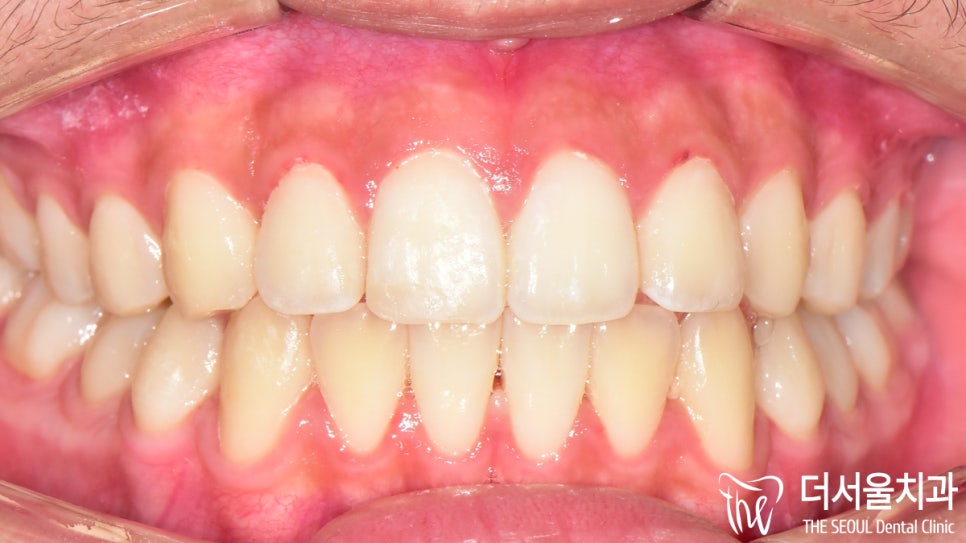

전과는 달리 벌어졌던 이 사이도

긴밀하게 붙어 있는 것이 확인되었으며

툭 튀어나와 있던 돌출입도 개선이 되었습니다.

인비절라인 을 사용한 덕인지

이갈이 가 심한데도 불구하고

구강 내 상처나 치아 마모 등이 나타나지 않았네요.